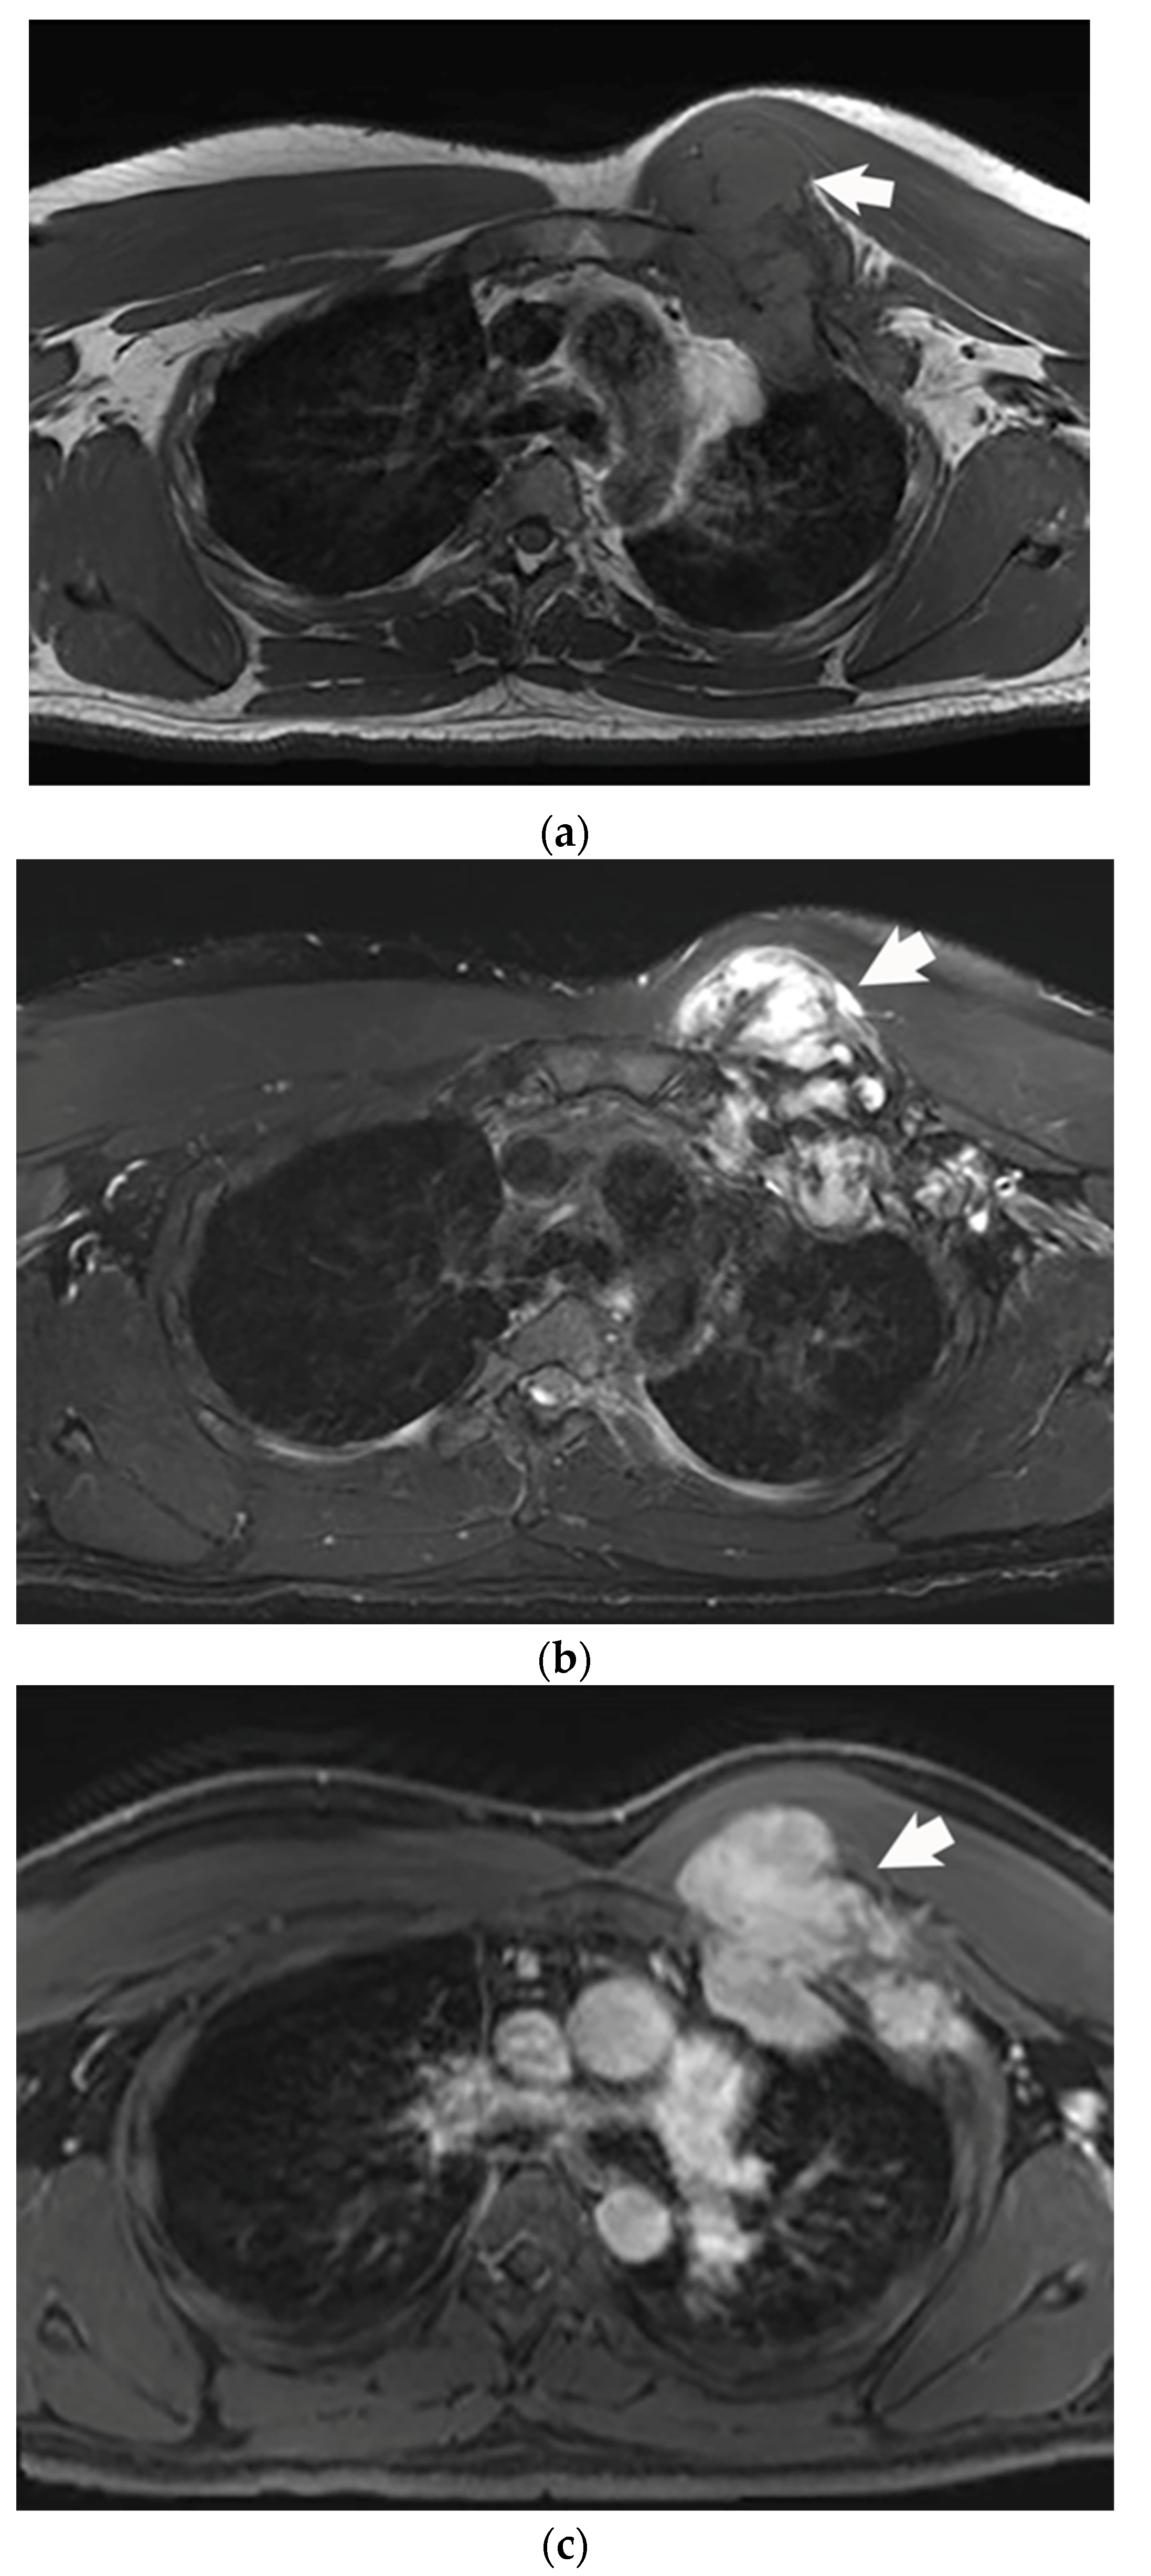

4.3. Cryoablation

- Kujak, J.L.; Liu, P.T.; Johnson, G.B.; Callstrom, M.R. Early experience with percutaneous cryoablation of extra-abdominal desmoid tumors. Skelet. Radiol. 2010, 39, 175–182. [Google Scholar] [CrossRef]

- Havez, M.; Lippa, N.; Al-Ammari, S.; Kind, M.; Stoeckle, E.; Italiano, A.; Gangi, A.; Hauger, O.; Cornelis, F. Percutaneous Image-Guided Cryoablation in Inoperable Extra-abdominal Desmoid Tumors: A Study of Tolerability and Efficacy. Cardiovasc. Interv. Radiol. 2014, 37, 1500–1506. [Google Scholar] [CrossRef]

- Schmitz, J.J.; Schmit, G.D.; Atwell, T.D.; Callstrom, M.R.; Kurup, A.N.; Weisbrod, A.J.; Morris, J.M. Percutaneous cryoablation of extraabdominal desmoid tumors: A 10-year experience. Am. J. Roentgenol. 2016, 207, 190–195. [Google Scholar] [CrossRef]

- Redifer Tremblay, K.; Lea, W.B.; Neilson, J.C.; King, D.M.; Tutton, S.M. Percutaneous cryoablation for the treatment of extra-abdominal desmoid tumors. J. Surg. Oncol. 2019, 120, 366–375. [Google Scholar] [CrossRef]

- Saltiel, S.; Bize, P.E.; Goetti, P.; Gallusser, N.; Cherix, S.; Denys, A.; Becce, F.; Tsoumakidou, G. Cryoablation of extra-abdominal desmoid tumors: A single-center experience with literature review. Diagnostics 2020, 10, 556. [Google Scholar] [CrossRef] [PubMed]

- Bouhamama, A.; Lame, F.; Mastier, C.; Cuinet, M.; Thibaut, A.; Beji, H.; Ricoeur, A.; Blay, J.-Y.; Pilleul, F. Local Control and Analgesic Efficacy of Percutaneous Cryoablation for Desmoid Tumors. Cardiovasc. Interv. Radiol. 2020, 43, 110–119. [Google Scholar] [CrossRef] [PubMed]

- Yan, Y.Y.; Walsh, J.P.; Munk, P.L.; Mallinson, P.I.; Simmons, C.; Clarkson, P.W.; Jayaram, P.R.; Heran, M.K.; Ouellette, H.A. A Single-Center 10-Year Retrospective Analysis of Cryoablation for the Management of Desmoid Tumors. J. Vasc. Interv. Radiol. 2021, 32, 1277–1287. [Google Scholar] [CrossRef] [PubMed]

- Johnston, E.; Alves, A.; Messiou, C.; Napolitano, A.; Strauss, D.; Hayes, A.; Smith, M.; Benson, C.; Jones, R.; Gennatas, S.; et al. Percutaneous cryoablation for desmoid fibromatosis: Initial experience at a UK centre. Clin Radiol. 2022, 77, 784–793. [Google Scholar] [CrossRef]

- Auloge, P.; Garnon, J.; Robinson, J.M.; Thenint, M.-A.; Koch, G.; Caudrelier, J.; Weiss, J.; Cazzato, R.L.; Kurtz, J.E.; Gangi, A. Percutaneous cryoablation for advanced and refractory extra-abdominal desmoid tumors. Int. J. Clin. Oncol. 2021, 26, 1147–1158. [Google Scholar] [CrossRef]

- Vora, B.M.K.; Munk, P.L.; Somasundaram, N.; Ouellette, H.A.; Mallinson, P.I.; Sheikh, A.; Kadir, H.A.; Tan, T.J.; Yan, Y.Y. Cryotherapy in extra-abdominal desmoid tumors: A systematic review and metaanalysis. PLoS ONE 2021, 16, e0261657. [Google Scholar] [CrossRef]

- Kurtz, J.-E.; Buy, X.; Deschamps, F.; Sauleau, E.; Bouhamama, A.; Toulmonde, M.; Honoré, C.; Bertucci, F.; Brahmi, M.; Chevreau, C.; et al. CRYODESMO-O1: A prospective, open phase II study of cryoablation in desmoid tumour patients progressing after medical treatment. Eur. J. Cancer 2021, 143, 78–87. [Google Scholar] [CrossRef]